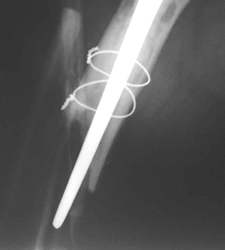

Ein Femurnagel wurde so zugerichtet, dass mit ihm die Prothesenspitze in einer Länge von 8 cm aufgefädelt wurde. Der Nagel wurde durch das Knie hindurch eingebracht. Distal wurde der Nagel verriegelt. Belastungsstabilität lag vor.